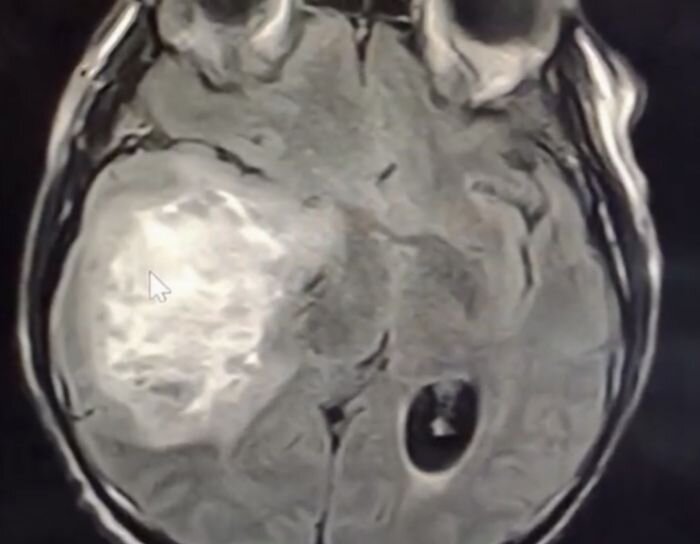

Features of CT and MRI imaging in astrocytomas

Astrocytomas of 1 — 4 degrees of malignancy